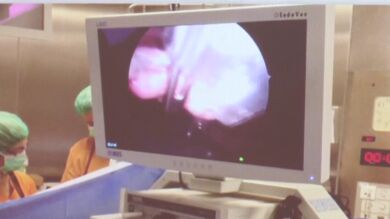

El Hospital Vall d'Hebrón de Barcelona ha presentado una nueva técnica del servicio de cirugía pediátrica que usa imanes para mover tejidos y órganos, lo que permite trabajar más fácilmente y reducir el número de incisiones.

Este instrumento hace la función de una pinza quirúrgica pero se puede dirigir desde el exterior con un imán más potente y logra reducir el número de cortes. "Menos incisiones significa menos dolor y menos cicatrices", ha subrayado Giné, que además de destacar la reducción del dolor postoperatorio y las facilidades para trabajar que otorga el imán, ha puesto en valor la reducción de cicatrices."En niños tenemos la obsesión de dejar las mínimas marcas posibles de cara a la vida adulta", ha subrayado. Esta técnica ha permitido que operaciones como la extirpación de la vesícula biliar, que anteriormente requería entre 3 o 4 incisiones, se pueda hacer con una sola incisión por el ombligo.

El manejo del instrumento es muy sencillo, según Giné, que también ha destacado la mejora en la precisión: "Cuando expones mejor los tejidos, la ejecución quirúrgica es más precisa y por lo tanto más segura para el paciente". El imán, que está unido a una pinza que se engancha a las vísceras o tejidos que se quiera mover, se introduce a través del corte que se hace para introducir la cámara u otros aparatos y permite ampliar el espacio de los cirujanos para trabajar, ya que es menos aparatoso que una pinza quirúrgica.